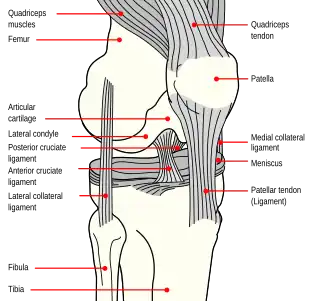

Anatomy of the knee

The patella is a triangular sesamoid bone that is embedded in tendon. It rests in the patellofemoral groove, an articular cartilage-lined hollow at the end of the thigh bone (femur) where the thigh bone meets the shin bone (tibia). Several ligaments and tendons hold the patella in place and allow it to move up and down the patellofemoral groove when the leg bends. The top of the patella attaches to the quadriceps muscle via the quadriceps tendon,[2] the middle to the vastus medialis obliquus and vastus lateralis muscles, and the bottom to the head of the tibia (tibial tuberosity) via the patellar tendon, which is a continuation of the quadriceps femoris tendon.[13] The medial patellofemoral ligament attaches horizontally in the inner knee to the adductor magnus tendon and is the structure most often damaged during a patellar dislocation. Finally, the lateral collateral ligament and the medial collateral ligament stabilize the patella on either side.[2] Any of these structures can sustain damage during a patellar dislocation.